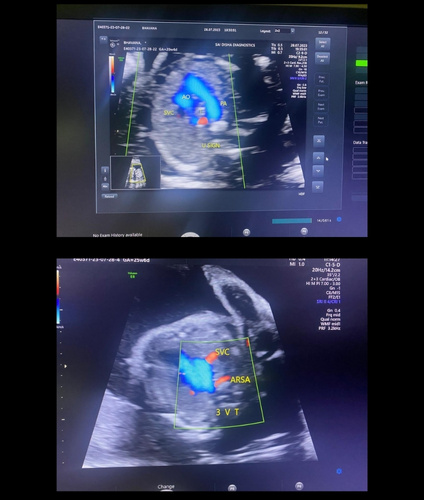

An ultrasound scan, also known as sonography, is a safe and non-invasive diagnostic procedure that uses sound waves to produce real-time images of the inside of the body. Unlike X-rays or CT scans, ultrasound does not use any radiation, making it especially suitable for monitoring pregnancies and for routine diagnostic imaging. During the procedure, a special gel is applied to the skin, and a device called a transducer is gently moved over the area of interest. The sound waves travel into the body and bounce back to create clear images of organs, tissues, and blood flow and fetus inside pregant mother.

Sai Disha Diagnostics offers high-resolution ultrasound imaging to support early and precise diagnosis across a wide range of medical conditions.

We offer pregnancy, abdominal, pelvic, thyroid, breast, and Doppler ultrasound scans.